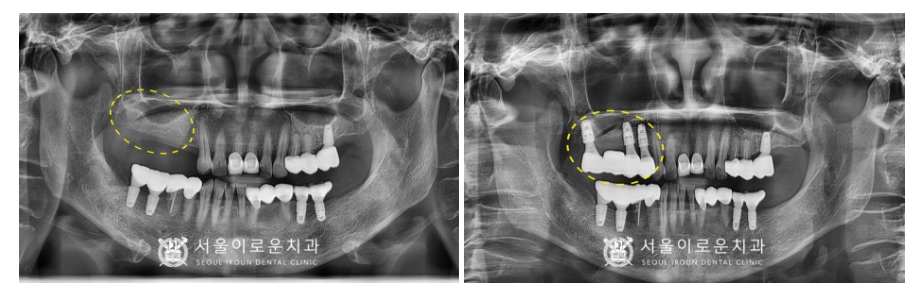

추후 3개월이 지나고

2차 수술을 통해

임플란트와 잇몸뼈가

단단하게 결합되었는지

골 유착을 확인할 수 있는

osstell beacon이라는 장비를 활용하여

안정 값을 확인한 뒤

잇몸 속에 묻혀있던 커버스크류를 제거하고

잇몸 밖으로 노.출 되는

healing abutment로 교체해주었으며,

보철 과정을 위한

인상 채득도 진행하였는데요.